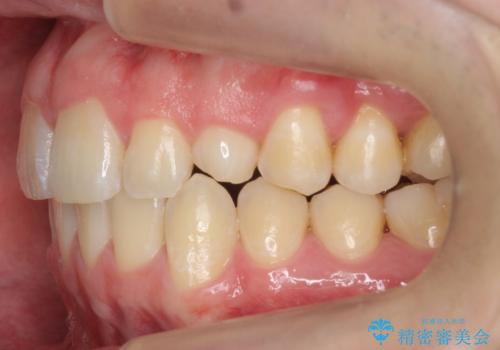

前歯のすき間、犬歯の異所萌出 乳歯を抜かずに矯正

- 前歯のすきまと八重歯を主訴に来院。

左上の乳犬歯が残っており、その下から生えてくるはずの犬歯(永久歯)が左上小臼歯部に萌出していました。

左上の乳犬歯は根もしっかりしていたため、

➀そのまま矯正する。乳歯がいずれダメになったときにそこはブリッジかインプラントを検討する

②乳歯は抜歯し、ブリッジかインプラントを矯正後に入れる

を提案し、➀を選択されました。

将来的にインプラントは希望されないとのことだったため、乳歯の部分は隙間を開けてインプラントを入れる用のすき間を確保するということは特に行いませんでした。

乳歯をそのまま並べたため、上顎の左右の犬歯の幅は非対称になっています。